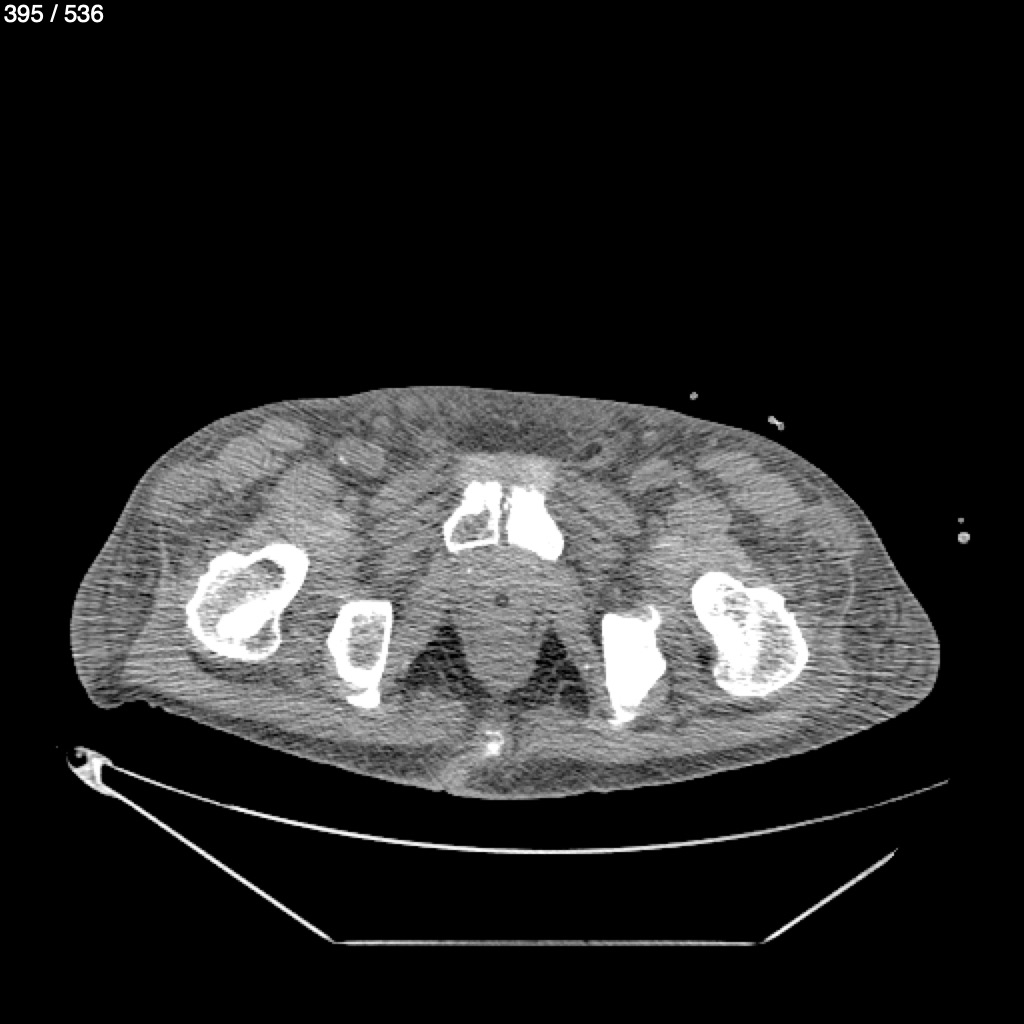

Angel Villalobos Palomeque 73 A - T.C Abdomen Simple